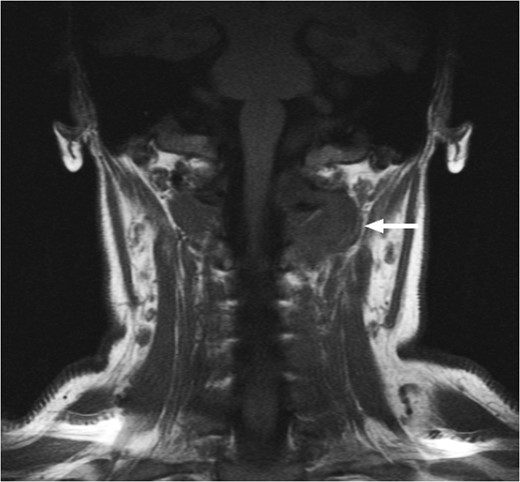

T1-weighted MRI scan showing the presence of scar tissue at the previous tumour site 6 months post-operatively. There is no evidence of residual tumour.